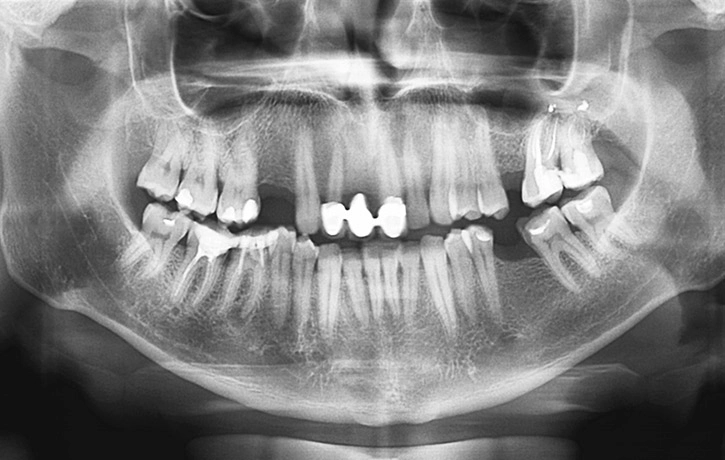

Missing Teeth Can Lead to Jaw Bone Reduction Over Time

Many people mistakenly believe that a missing tooth is nothing but an aesthetic concern for their smile. However, there is a more serious result of tooth loss—the loss of bone volume in your jaw. After just one year with a missing tooth, there is on average a 25 percent decrease in bone volume. When a tooth is lost or extracted, the root below the gum line no longer stimulates the bone that once held it in place. This causes your jaw bone to recede, which can have consequences to the function of your bite, your facial appearance and the chance of dental implant placement. Dr. Howard Abrahams offers a solution to bone loss through bone grafting and sinus lift procedures.